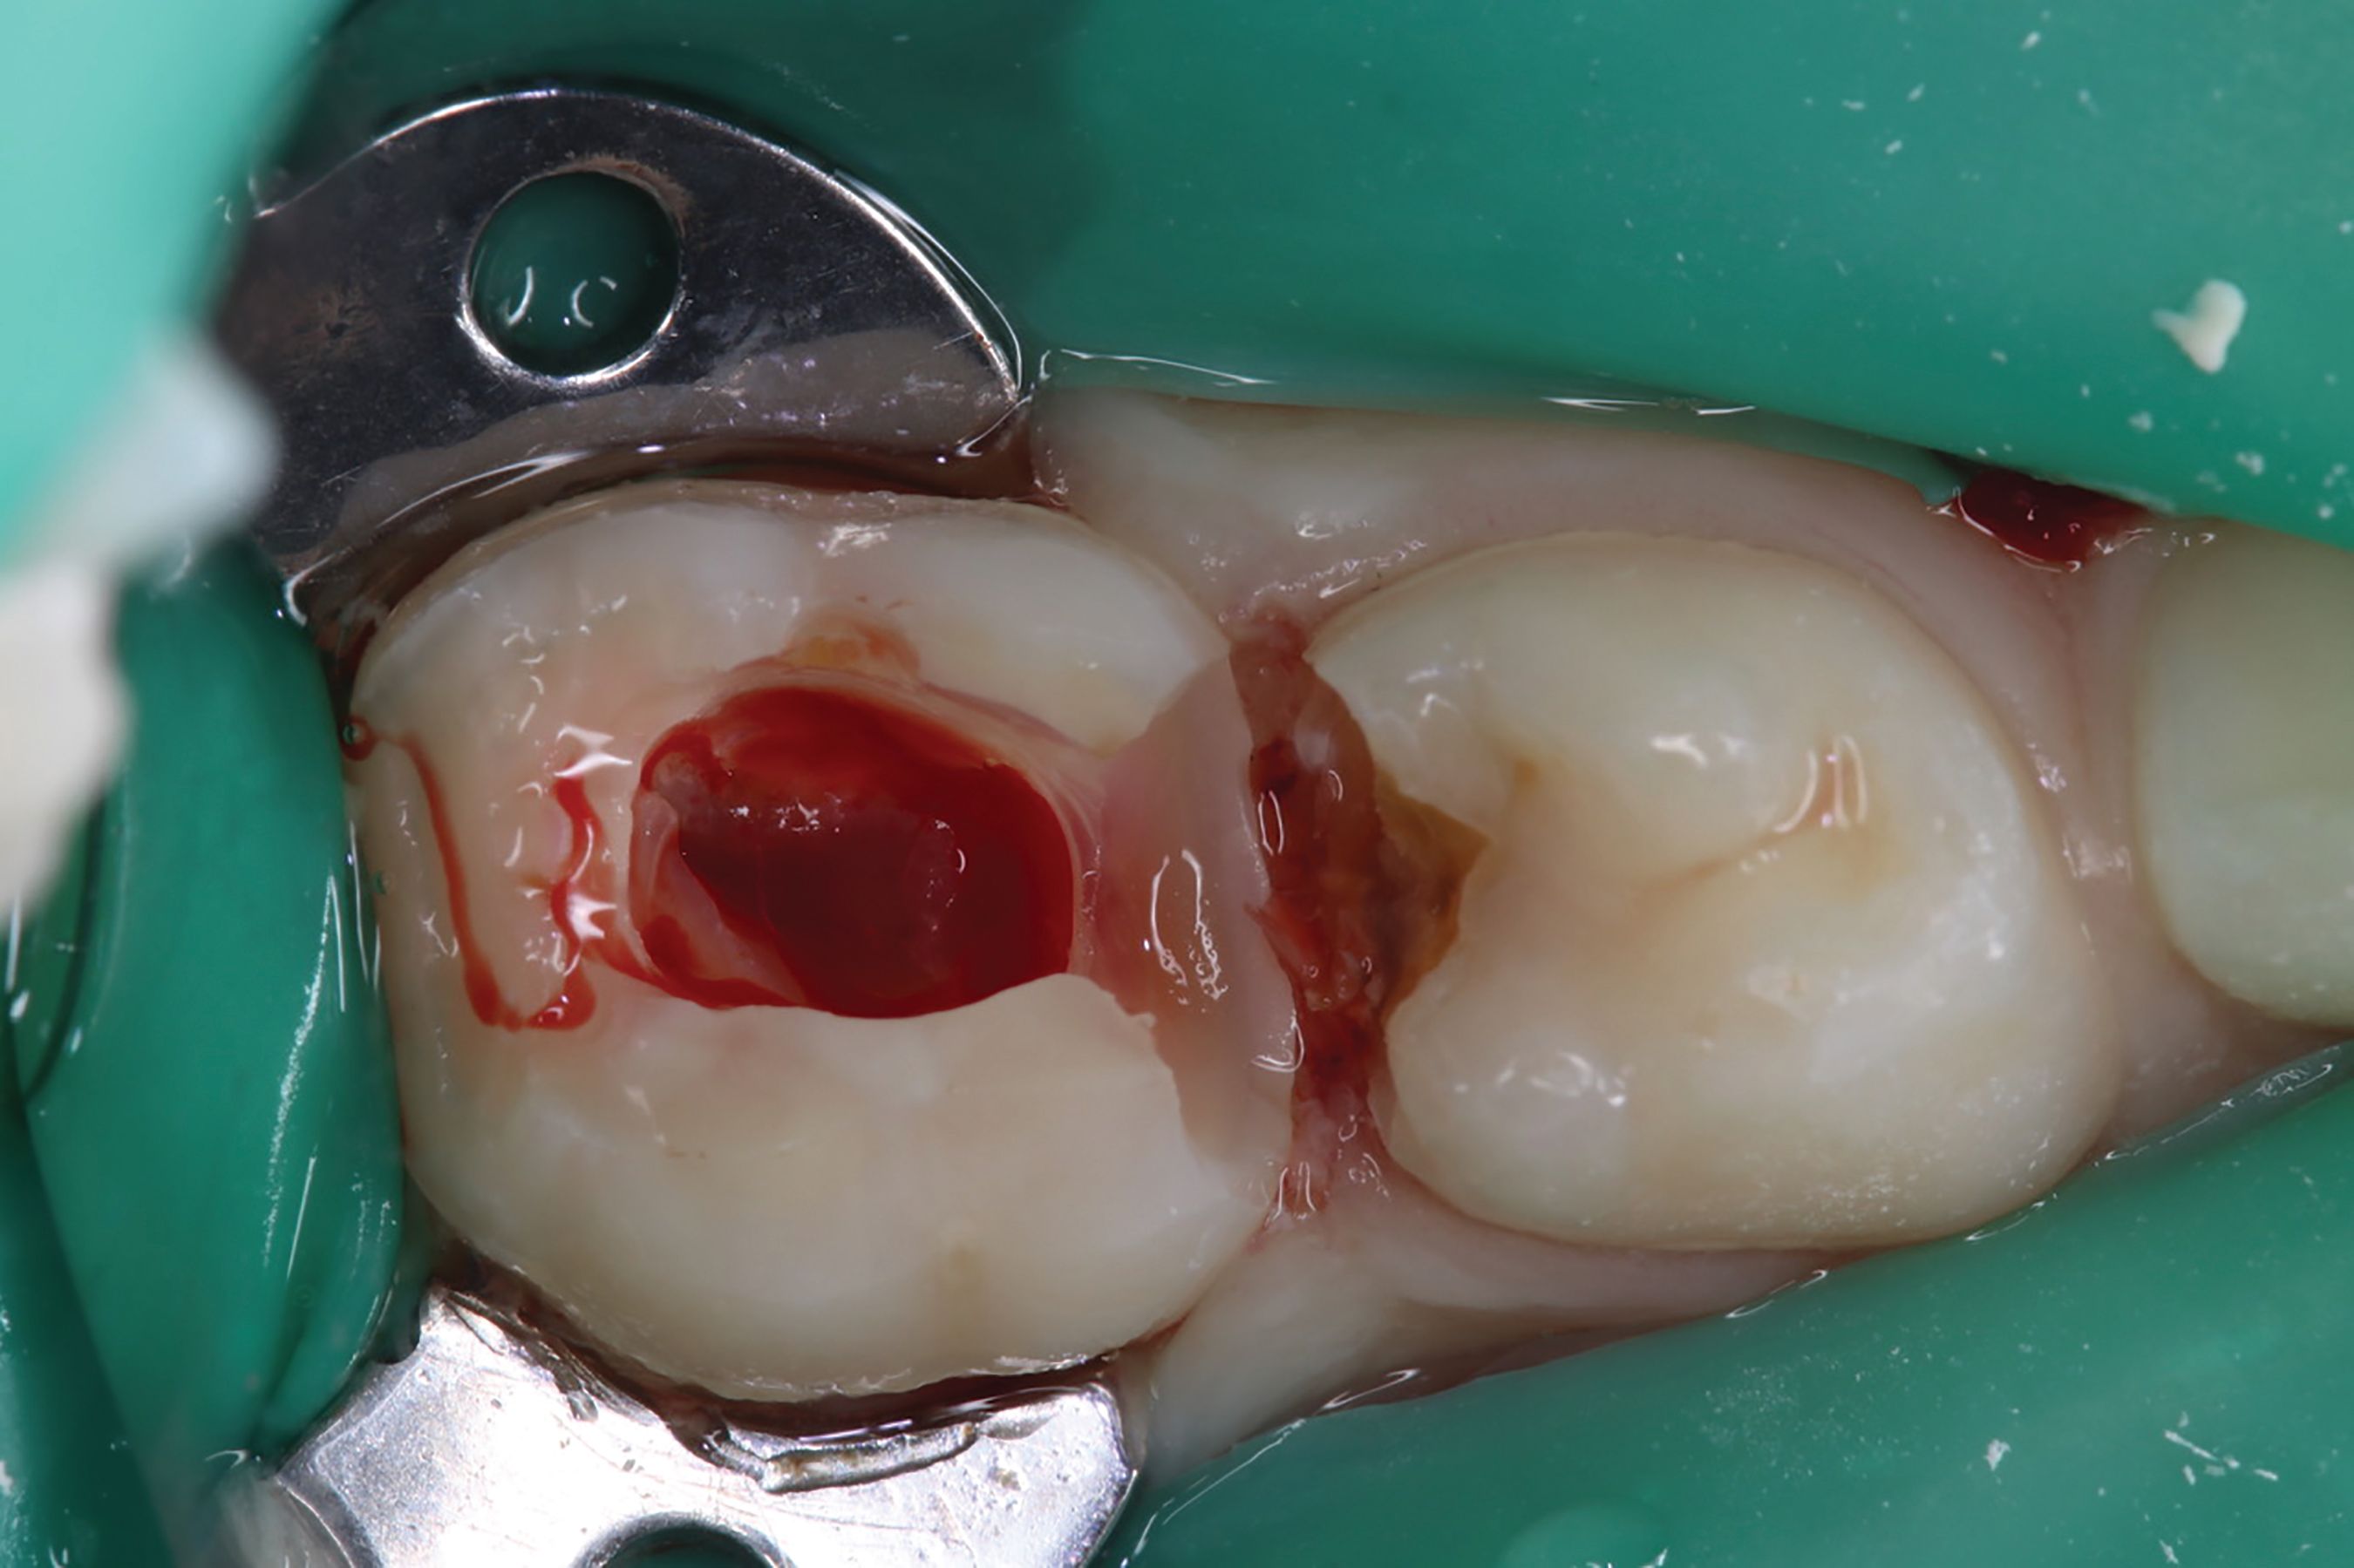

Fig. 2.

Amputation of coronal pulp chamber to the level of radicular pulp stumps was performed with NSK Dental slow speed large round bur #8, removing coronal pulp tissue with gentle upward motion (Fig. 2). Hemostasis is achieved with a saline-soaked sterile cotton pellet (Figs. 3-4). Figure 5 also illustrates hemostasis.

[ Figs. 1-9 ] Pre-operative view-primary second molar requiring pulpotomy procedure (Fig. 1). Amputation of coronal pulp chamber to level of radicular pulp stumps with NSK Dental’s slow speed large round bur #8, removing coronal pulp tissue with gentle upward motion (Fig. 2). Hemostasis achieved with saline-soaked sterile cotton pellet (Figs. 3 & 4). Hemostasis achieved (Fig. 5). Extrusion of TheraCal PT into pulp chamber, being sure to reach base of coronal pulp chamber with material and without voids or bubbles and light cure (Figs. 6 & 7). Cured TheraCal PT (Fig. 8). Full-coverage stainless-steel crown (Fig. 9).